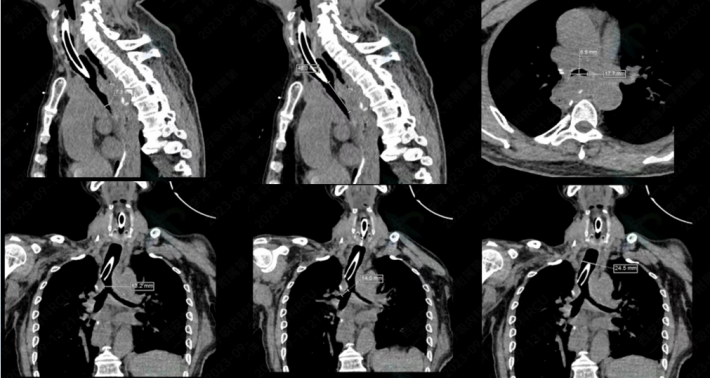

测量气道,定制硅酮支架,然后置入“L”型硅酮支架(图19,图20)

图19  测量气道,定制硅酮支架

图20  置入“L”型硅酮支架